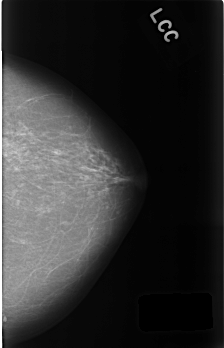

C_0454_1.LEFT_CC

LEFT_CC LINES 4512 PIXELS_PER_LINE 2912 BITS_PER_PIXEL 12 RESOLUTION 50 NON_OVERLAY